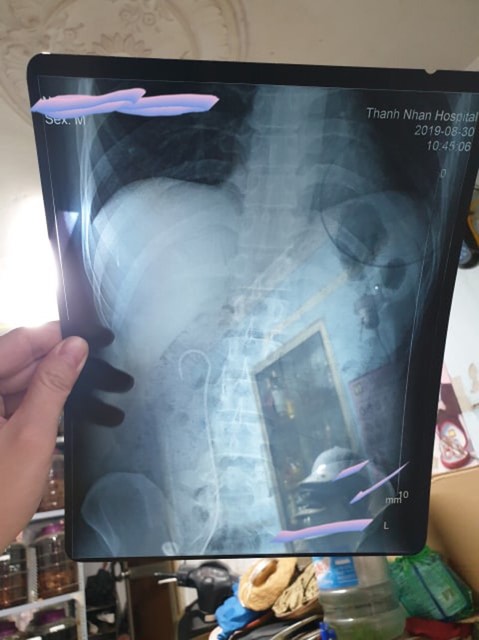

Thấy anh H như vậy, chị Y đưa chồng mình đến kiểm tra, chụp chiếu lại tại bệnh viện Thanh Nhàn. Khi chụp X-quang, chị Y và anh H mới phát hiện ra ống JJ như hình móc câu nằm trong người, dài hơn 20 cm từ thận xuống bàng quang. Sau khi rút ống JJ ra thì anh H cảm thấy bình thường, không thấy đau và ra máu nữa. Chị Y còn bức xúc hơn nữa khi bệnh viện Thanh Nhàn yêu cầu nhà chị phải đưa thêm 2 triệu đồng thì mới đồng ý mổ cho anh H.

Ống JJ như hình móc câu, dài hơn 20 cm được bệnh nhân phản ánh bác sỹ để quên khi mổ.